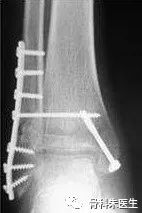

复查X光片以确定骨折愈合情况,X光片已显示明显骨痂生长即可开始负重练习。